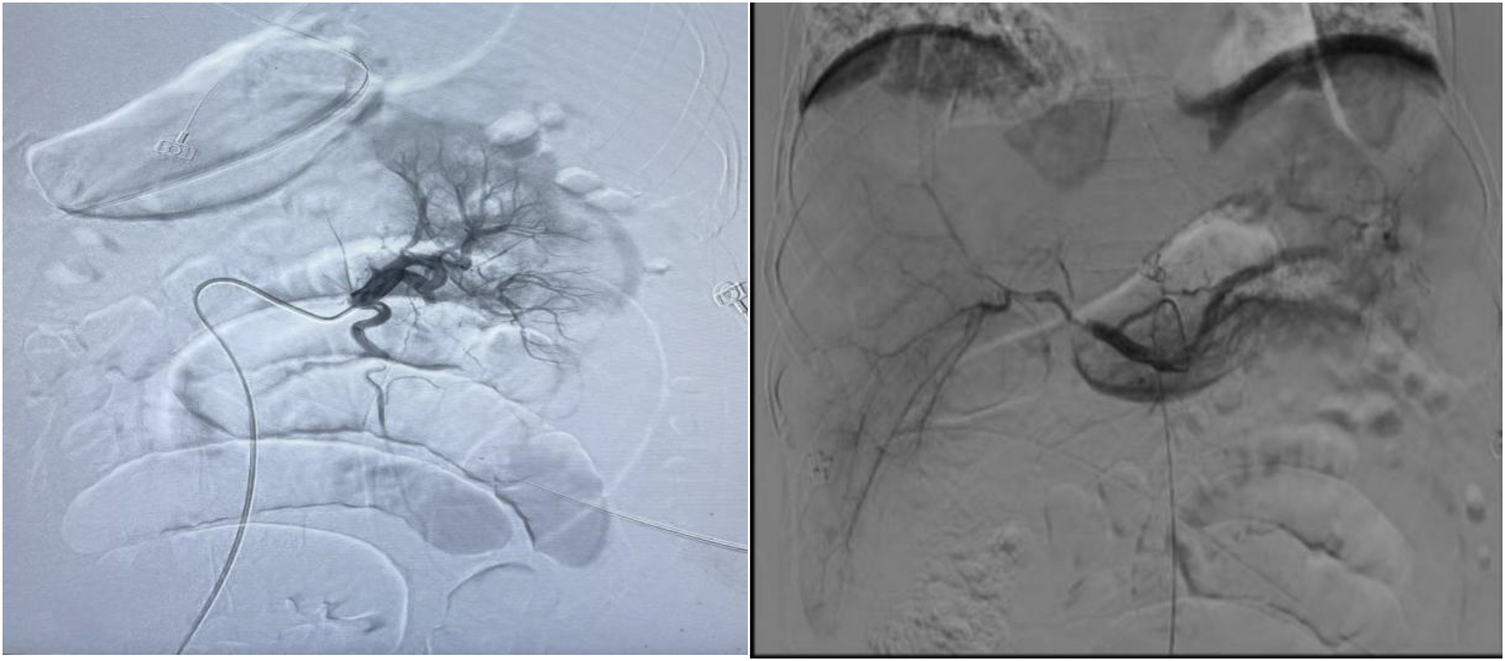

Following the removal of the temporary pacemaker and IABP immediately once CTA detected thrombi in several branches of the abdominal aorta on the 12th day of hospitalization (PCI and IABP), emergency celiac arteriography was promptly performed. Urokinase thrombolysis and interventional thrombectomy were performed at the main renal arteries, as well as the gastroduodenal, left hepatic, and right hepatic arteries. The first thrombolysis procedure completed. On the 14th day, the intestinal sounds remained weak, one time per minute the patient's abdominal circumference (97 cm) and intra-abdominal pressure (7.3 cmH2O) was stable. Subsequent follow-up examinations revealed a significant reduction in thrombus burden.

On the 4th day after the first thrombolysis procedure, celiac arteriography was performed again. The blood flow perfusion of the left and right hepatic arteries and bilateral renal arteries was significantly improved. Further thrombolysis with urokinase was administered to the left renal artery and the main trunk of the superior mesenteric artery. The second thrombolysis procedure was completed (Figure 2).

Figure 2

Urokinase dissolves thrombus at the opening of both renal arteries and superior mesenteric arteries, while loach guide wire pulls thrombus at the gastroduodenal artery, left hepatic artery, right hepatic artery, and superior mesenteric artery.